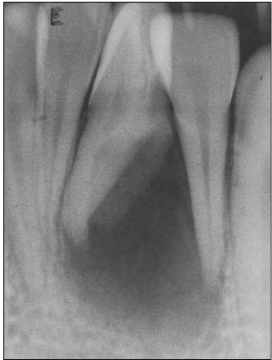

Diagnostic intraoral radiograph.

jkacd-31-161-g002.jpg

Figure 2 Diagnostic intraoral radiograph.